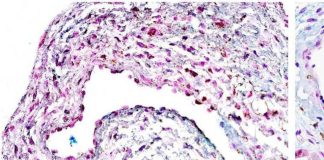

Cáncer de colon: el silencioso avance del segundo cáncer más frecuente en Chile que puede prevenirse a tiempo

Cáncer de colon: el silencioso avance del segundo cáncer más frecuente...